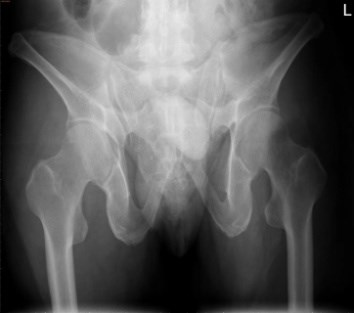

病历资料:该患者为中年男性,因车祸伤致骨盆骨折合并髋外侧及后侧大面积Morel-Lavallee 损伤。

术前影像